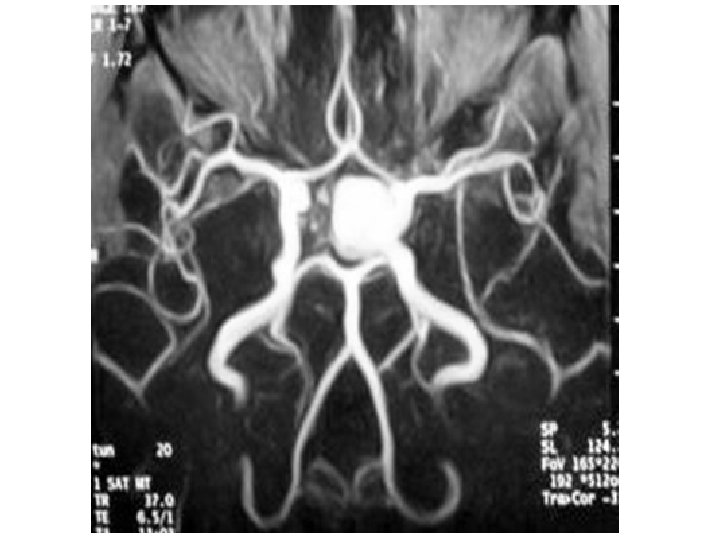

Aneurysm of ACI

Patrs of aa. cerebri • a. cerebri ant. – pars precommunicalis; segmentum A 1 – pars postcommunicalis; segmentum A 2 • a. cerebri media – pars sphenoidealis/horizontalis; segmentum M 1 – pars insularis; segmentum M 2 • a. cerebri post. – pars precommunicalis; segmentum P 1 – pars postcommunicalis; segmentum P 2

Aneurysma ACA